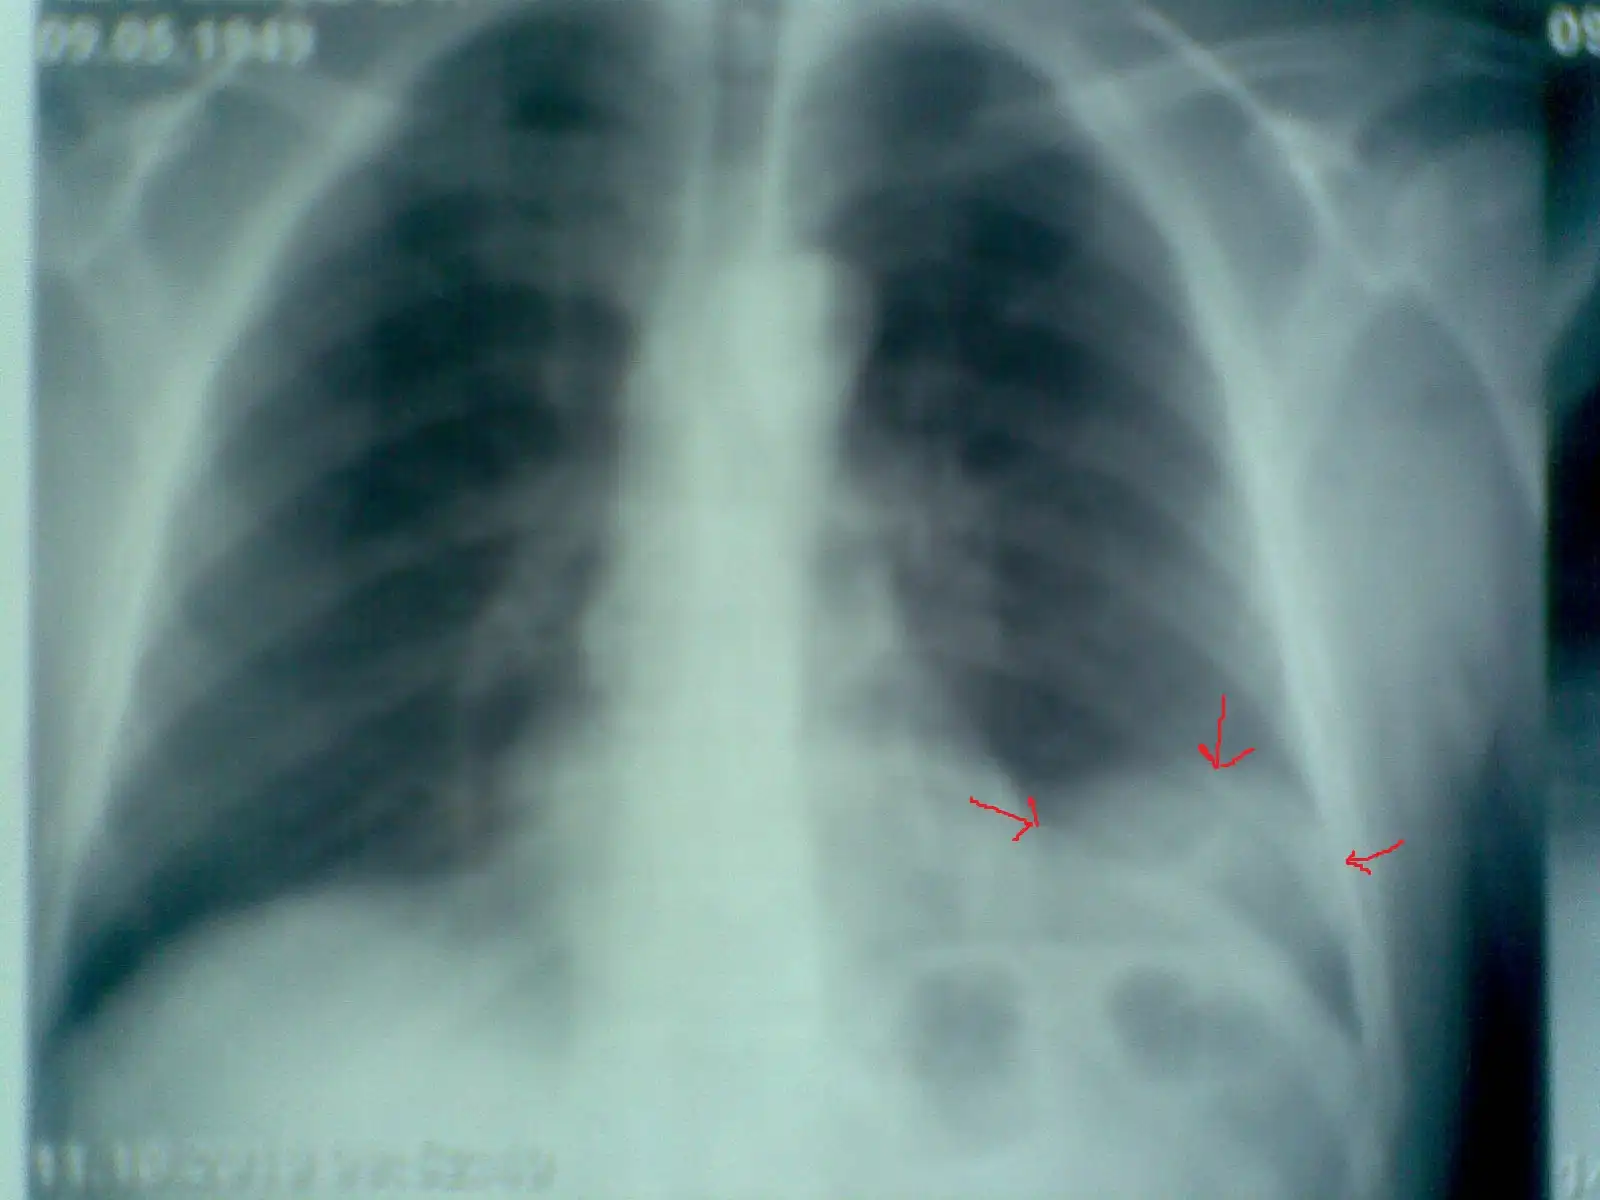

Пациент № 4: